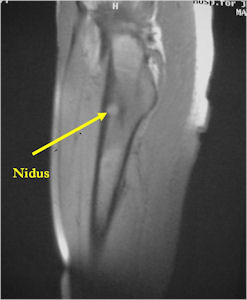

MRI:

- MRI should be performed with gadolinium if possible. The nidus should enhance with gadolinium

- An osteoid osteoma on MRI may mimic findings of a malignant tumor such as Ewing’s sarcoma or osteomyelitis because of the presence of marrow and soft tissue edema that can be extensive and make it difficult to discern a nidus.

- CT is more useful for detecting the nidus if there is extensive edema

- Osteoid Osteomas are Intermediate intensity on T1

- High intensity on T2 in areas of nidus and surrounding edema

- Reactive marrow edema may obscure the lesion on T2

- MRI is good for detecting synovitis and joint effusion with intraarticular osteoid osteomas